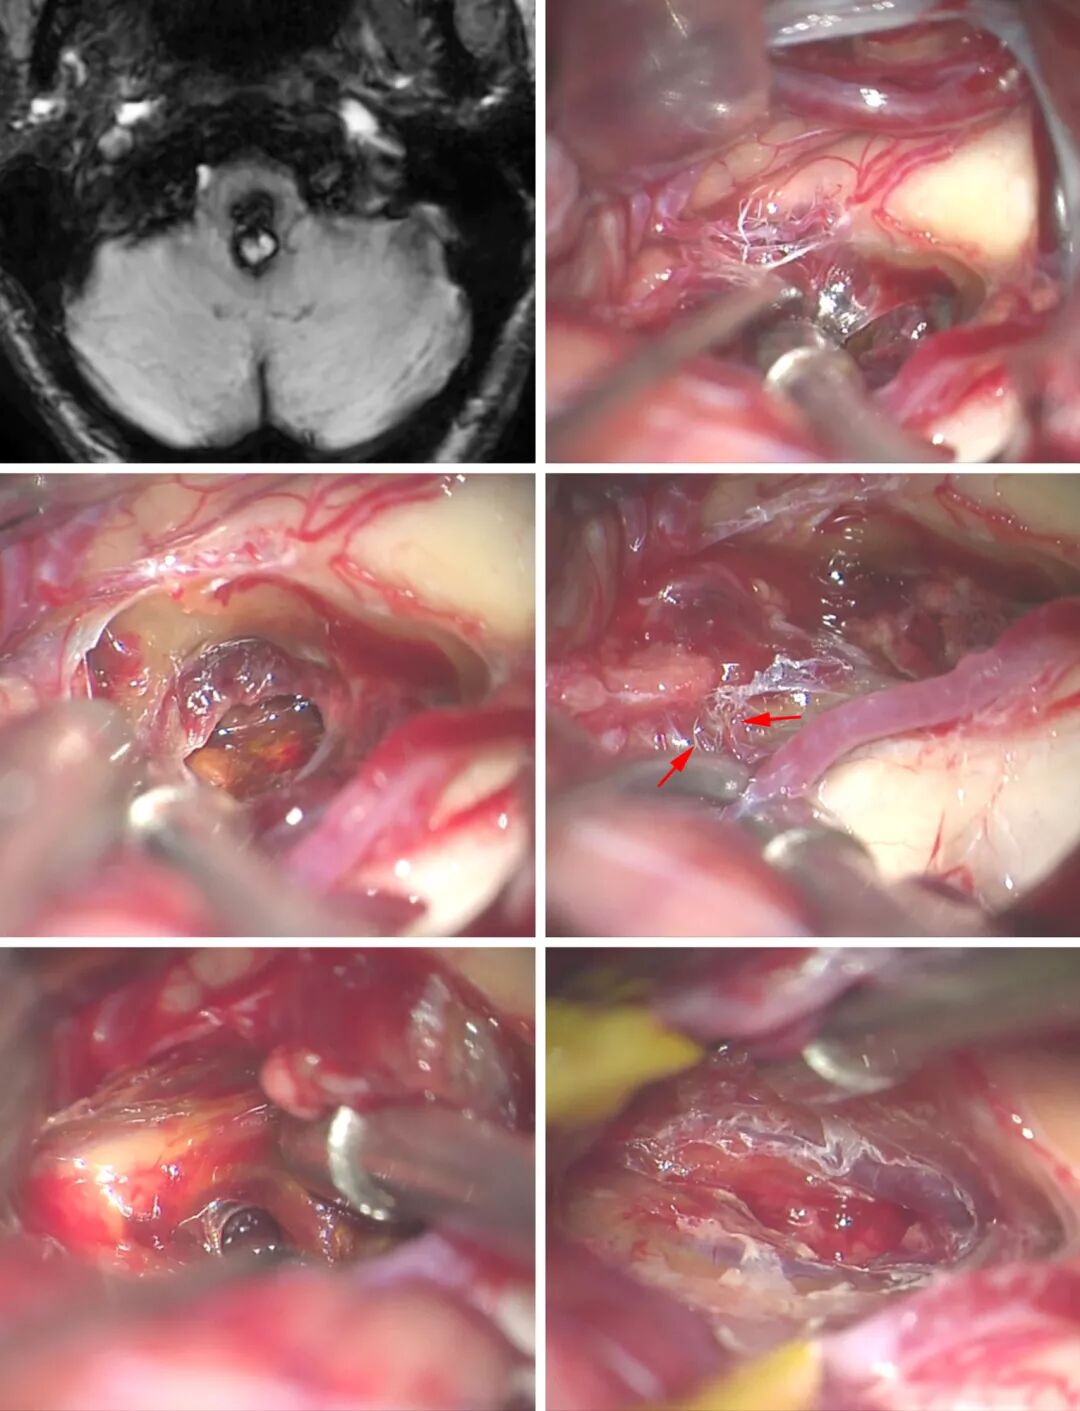

图11:这个延髓后部的CM经枕下开颅显露,早期确认了CM的终末供血血管(上排图像)。CM内的血肿已清除减压,显露起源于对侧PICA的其他终末供血血管(中排,箭号)。CM可有分隔(左下图),因此必须彻底、谨慎地检查手术残腔,才能做到完全切除病灶(右下图)。